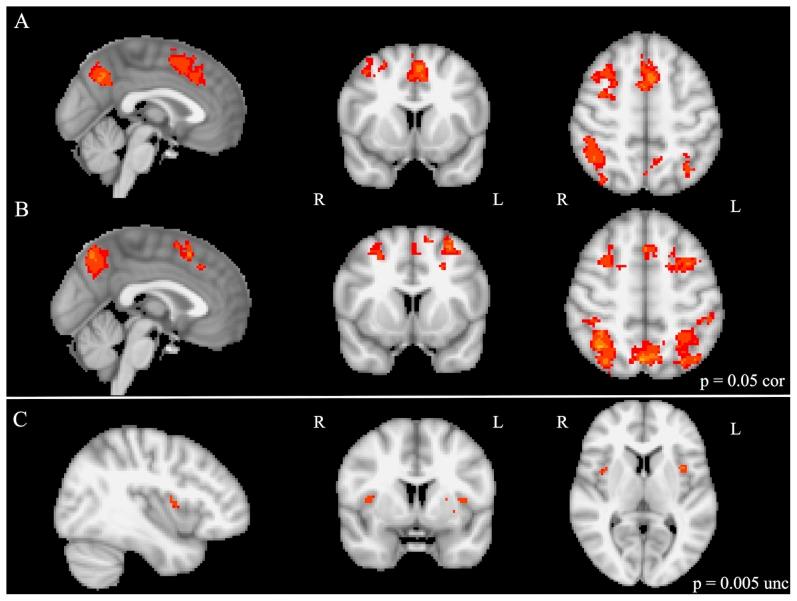

Executive functions (EF) are cognitive capacities that allow for planned, controlled behavior and strongly correlate with academic abilities. Several extracurricular activities have been shown to improve EF, however, the relationship between musical training and EF remains unclear due to methodological limitations in previous studies. To explore this further, two experiments were performed; one with 30 adults with and without musical training and one with 27 musically trained and untrained children (matched for general cognitive abilities and socioeconomic variables) with a standardized EF battery. Furthermore, the neural correlates of EF skills in musically trained and untrained children were investigated using fMRI. Adult musicians compared to non-musicians showed enhanced performance on measures of cognitive flexibility, working memory, and verbal fluency. Musically trained children showed enhanced performance on measures of verbal fluency and processing speed, and significantly greater activation in pre-SMA/SMA and right VLPFC during rule representation and task-switching compared to musically untrained children. Overall, musicians show enhanced performance on several constructs of EF, and musically trained children further show heightened brain activation in traditional EF regions during task-switching. These results support the working hypothesis that musical training may promote the development and maintenance of certain EF skills, which could mediate the previously reported links between musical training and enhanced cognitive skills and academic achievement.

执行功能(EF)是一种认知能力,它能促成有计划、可控制的行为,并且与学业能力密切相关。已有研究表明,多种课外活动可改善执行功能,然而,由于先前研究存在方法学上的局限性,音乐训练与执行功能之间的关系仍不明确。为进一步探究这一关系,我们进行了两项实验:一项实验的对象是30名有或没有音乐训练经历的成年人,另一项实验的对象是27名接受过和未接受过音乐训练的儿童(在一般认知能力和社会经济变量方面进行了匹配),并使用标准化的执行功能测试组对他们进行测试。此外,我们还利用功能磁共振成像(fMRI)研究了接受过和未接受过音乐训练的儿童在执行功能技能方面的神经关联。与非音乐家相比,成年音乐家在认知灵活性、工作记忆和言语流畅性方面的表现更优。接受过音乐训练的儿童在言语流畅性和处理速度方面表现更优,并且与未接受过音乐训练的儿童相比,在规则表征和任务切换过程中,其前辅助运动区/辅助运动区(pre-SMA/SMA)和右侧腹外侧前额叶皮层(right VLPFC)的激活程度明显更高。总体而言,音乐家在执行功能的多个方面表现更优,接受过音乐训练的儿童在任务切换过程中,其传统执行功能区域的大脑激活程度也更高。这些结果支持了以下工作假设:音乐训练可能促进某些执行功能技能的发展和维持,这可能介导了先前报道的音乐训练与认知技能提升及学业成绩之间的联系。